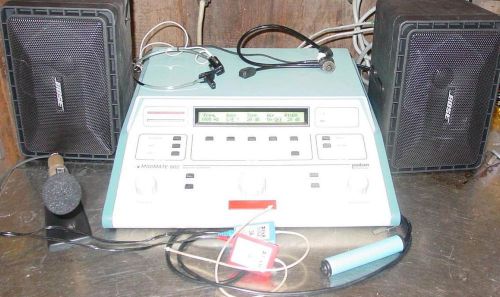

MIDIMATE 602 DIAGNOSTIC AUDIOMETER